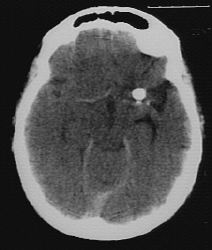

2. The paediatrician suspects shaken baby syndrome and order some

radiological investigations. The following pictures are consistent

with the suspicion: